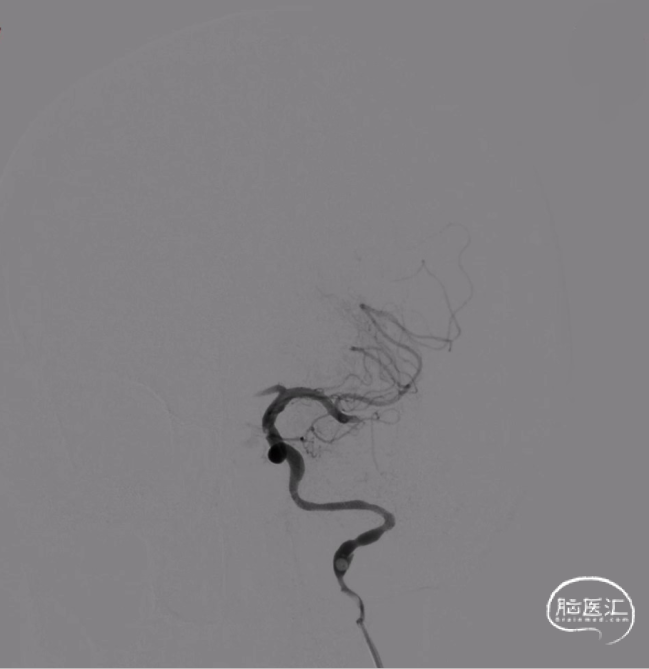

将6F长鞘在泥鳅导丝和5F多功能导管引导下送至左侧颈总动脉,撤出导丝,造影路途下在泥鳅导丝引导下将5F多功能导管缓慢带至C2段,低压力下造影,证实远端真腔,同时可见左侧颈内动脉C3-C5少许附壁血栓,左侧大脑中动脉M1分叉前血栓导致远端闭塞。

随后将微导丝(0.014inch/300cm)沿5F多功能导管送入,长导丝交换技术将5F多功能导管撤出体外,随后沿微导丝送入微导管(0.021inch/150cm)至左侧大脑中动脉M1段下干以远,同时将6F血栓抽吸导管系统(ACE 132cm)同轴技术跟进,到达左侧大脑中动脉M1段血栓位置,接近血栓后,撤出微导丝、微导管,持续负压抽吸,同时缓慢撤出体外,抽吸出多块暗红色血栓,同时在颈内动脉C3-C5段反复抽吸,随后复查造影见左侧大脑中动脉血流复通,血栓消失,左侧颈内动脉C3-C5段附壁血栓消失。

随后将微导丝携带微导管越过夹层段,将6F血栓抽吸导管系统同轴技术跟进,将6F长鞘沿6F血栓抽吸导管系统(ACE/132cm)送至左侧颈内动脉C2段,随后撤出微导管以及6F血栓抽吸导管系统,沿微导丝尾端送入颈动脉支架(Wallstent 9mm*40mm),定位准确后释放支架,再次行左侧颈动脉造影,左侧颈内动脉全程显影。